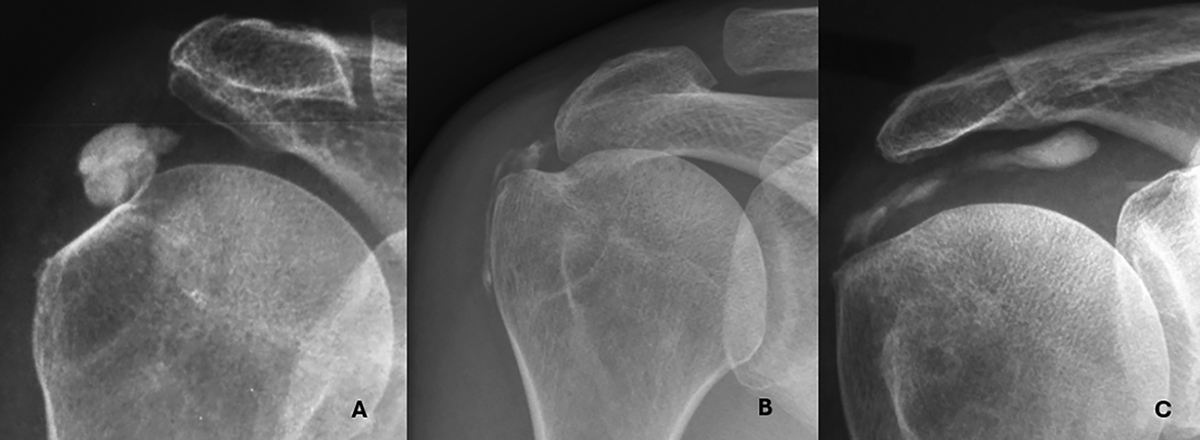

Representative imaging features of Type I and Type II calcifications. A. Type I – In situ calcification confined to the tendon, without signs of migration. Note the cortical sclerosis of the greater tuberosity adjacent to the deposit. B. Type II-a – Extension into the subacromial-subdeltoid bursa. C. Type II-b – Medial progression along the supraspinatus tendon, creating a characteristic “comet-tail” appearance.